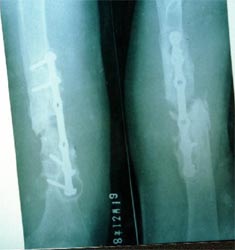

病例二、患者女性,20岁,肱骨中段骨折1年,骨不连形成。

带锁髓内钉固定骨折端提供支撑力,患者自体骨髓细胞经与松质骨和骨生长因子复合,

使没有细胞的植骨材料变成了有细胞的活骨。骨折在8个月后愈合。

手术后去除内固定